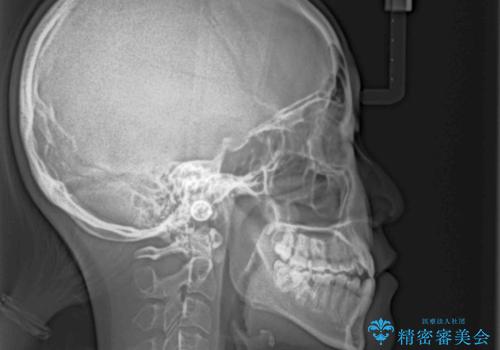

八重歯とオープンバイト 急速拡大装置を用いた矯正治療

- 前歯の開咬と、上顎前歯の八重歯やデコボコを気にして来院された患者様です。

上顎歯列が狭窄していたため、急速拡大装置により上顎骨を側方に拡大し、その後ワイヤー装置にて矯正治療を行うこととしました。

急速拡大装置で上顎骨を十分に拡大できたことで、非抜歯で八重歯を歯列に納めることができました。